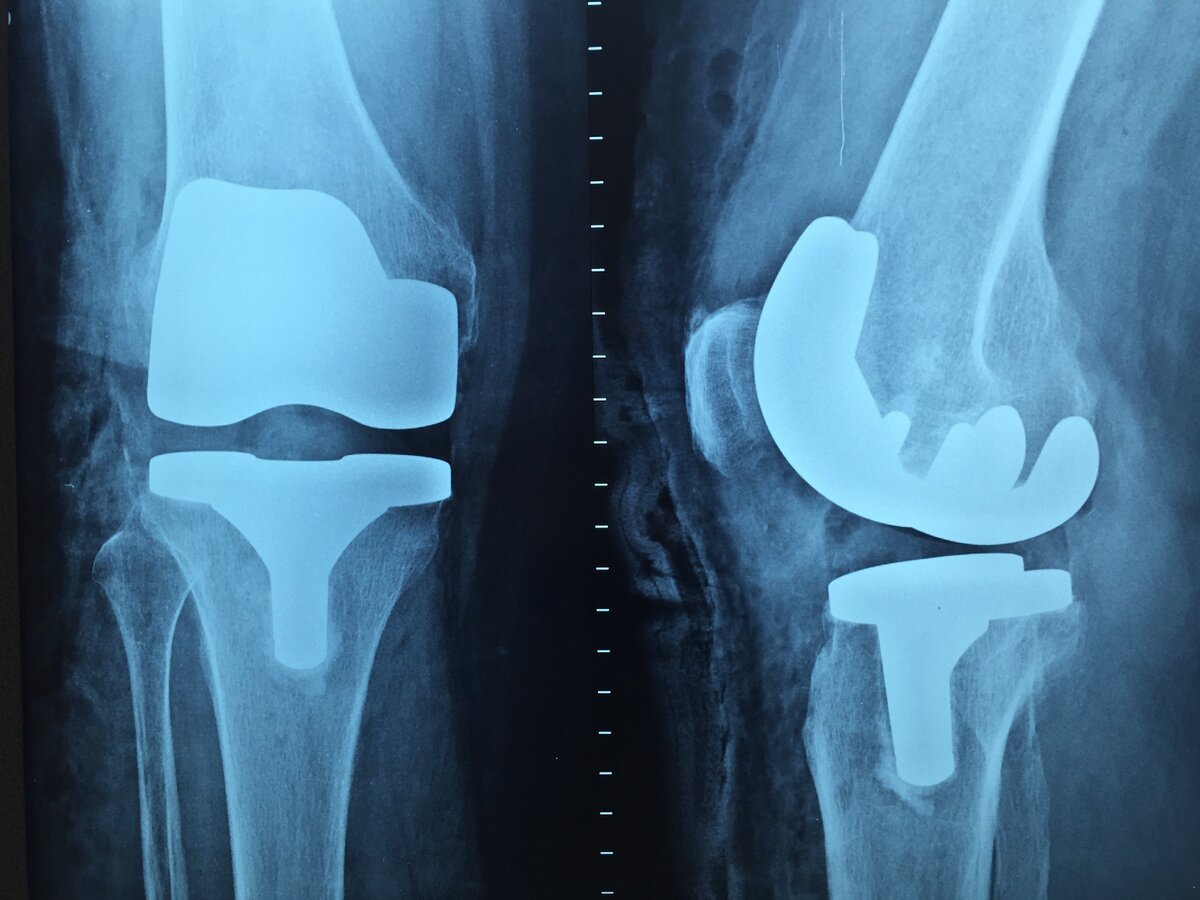

Я вышел из тяжелейшей ситуации, когда врачи предлагали единственное решение — замену сустава на искусственный, и вернулся к активным занятиям спортом и боевыми искусствами. Посмотрите на этот рентгеновский снимок. Как вы думаете, что это такое?

Рентгеновский снимок коленного сустава

Верно. Это искусственный сустав.

В конце концов боли в колене усилились так, что я не мог спать. Обратился в ЦИТО (Национальный медицинский исследовательский центр травматологии и ортопедии имени Н. Н. Приорова), в котором проходил практику после школы. Получил диагноз «артроз коленного сустава» и предложение от докторов счистить хрящи, и сделать металлическую вставку в сустав как на фото выше.